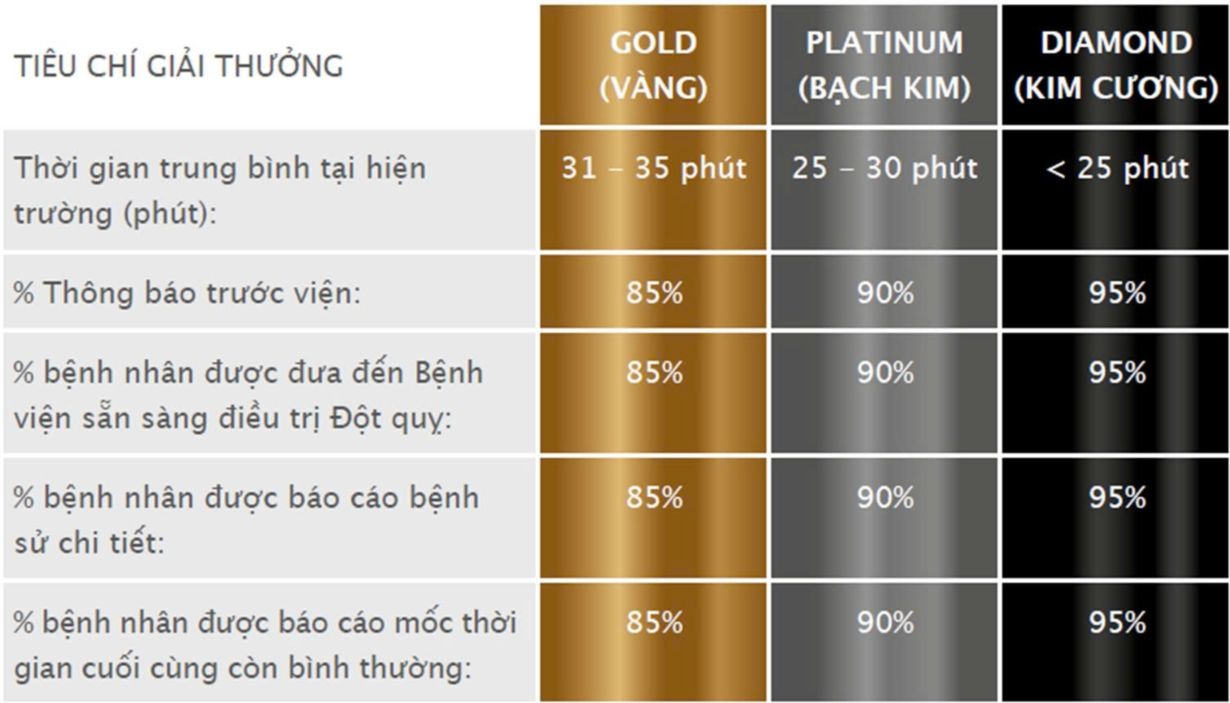

Trong khuôn khổ Hội nghị Liên minh Đột quỵ Toàn cầu (Global Stroke Alliance – GSA 2025) diễn ra từ ngày 25 – 26/7/2025 tại Hà Nội, Bệnh viện Thống Nhất tiếp tục được Tổ chức Đột quỵ Thế giới (WSO) trao tặng giải thưởng Kim Cương WSO Angels – mức công nhận cao nhất dành cho các đơn vị có chất lượng điều trị đột quỵ xuất sắc theo chuẩn quốc tế.

Mới đây, tại Hội nghị Liên minh Đột quỵ Toàn cầu (Global Stroke Alliance – GSA), Bệnh viện Đa khoa Châu Đốc (tiền thân là Bệnh viện Đa khoa khu vực tỉnh An Giang) đã được vinh danh với giải thưởng Kim Cương WSO Angels – chứng nhận cao nhất về chất lượng điều trị đột quỵ não do Tổ chức Đột quỵ Thế giới (WSO) trao tặng.

Trung tâm Cấp cứu 115 nhận giải Kim cương EMS Angels – Nâng tầm chất lượng cấp cứu đột quỵ ngoại viện

Vừa qua, Trung tâm Cấp cứu 115 TPHCM chính thức công bố đạt chứng nhận Kim cương – mức cao nhất trong hệ thống đánh giá EMS Angels cho lĩnh vực cấp cứu đột quỵ ngoài bệnh viện. Đây là cột mốc khẳng định năng lực và chất lượng của hệ thống cấp cứu ngoại viện thành phố, hướng đến tiệm cận tiêu chuẩn quốc tế.